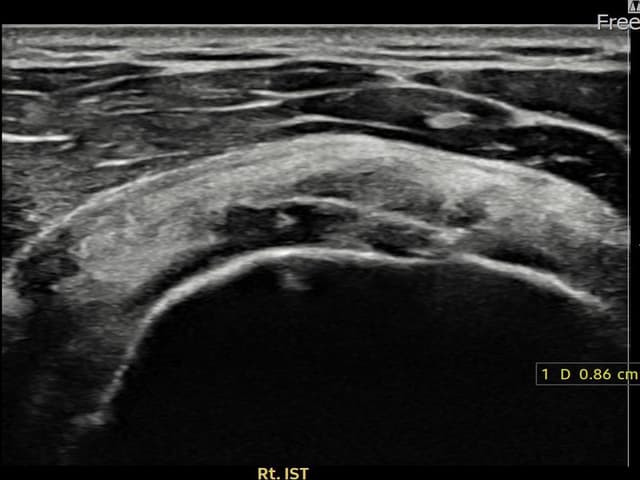

[촬영시기:22.08.13~22.10.29]

[어깨인대 축소봉합술] 우측 어깨 후방 통증과 팔을 바깥으로 돌릴 때 통증이 심해 내원하셨습니다.